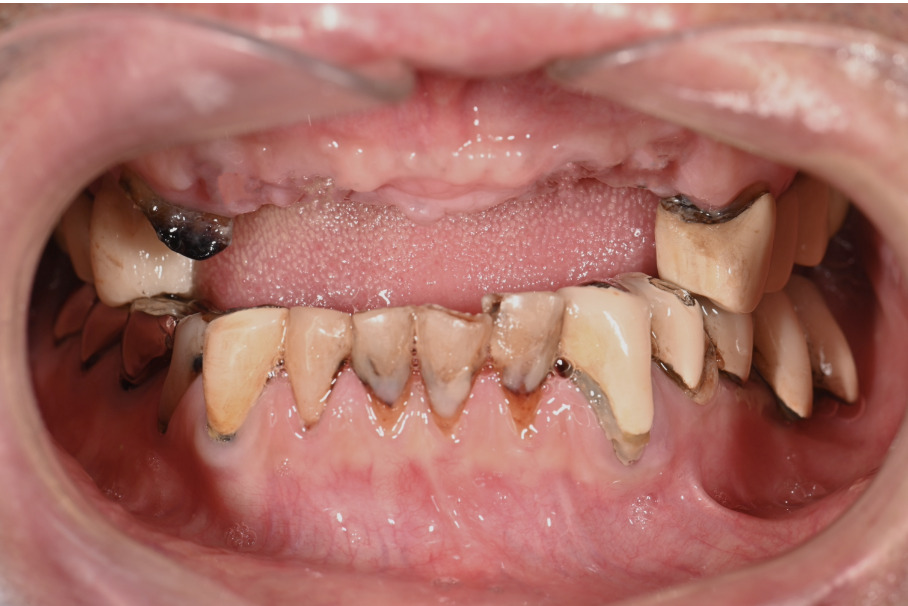

| 主訴 | 全体的にきれいにしたい |

|---|---|

| 治療内容 | 午前中に上下顎共に重度の歯周病、虫歯のため全ての歯を抜歯させていただき下顎はインプラントの土台を3本埋入し歯型を取り午後に上部構造(下顎全ての歯)を装着、上顎は一度総入れ歯を装着させていただきました。 治療が1日で完了しその日のうちに噛めるようになります。 |

| 治療期間 | 2回(1回目に資料取りをさせていただき2回目に下記の全ての治療をさせていただきました。) |

| 治療費 | 250万円 |

| 治療 リスク | 抜歯した部位などに関しては当日痛みが出ますので痛み止めなどを処方させていただきます |